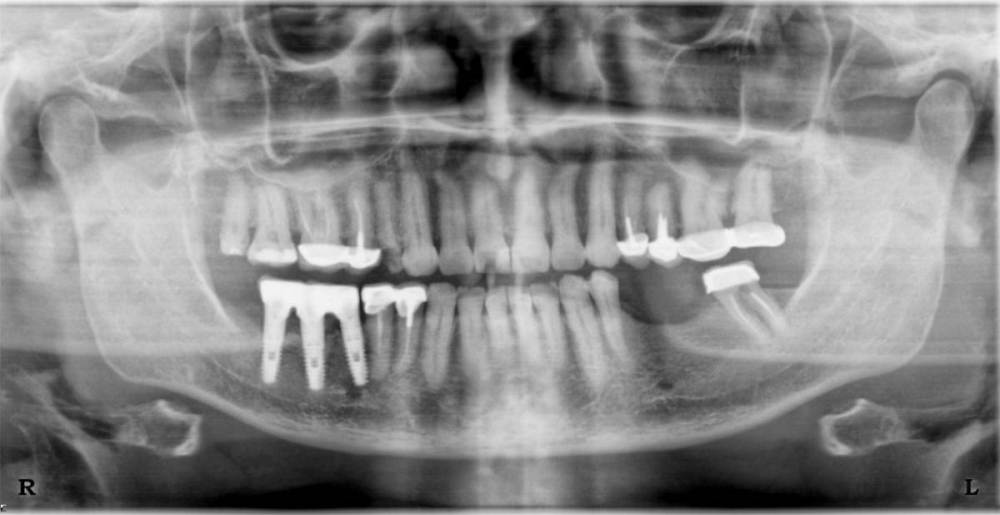

Dashik Опубликовано 16 июня, 2023 Поделиться Опубликовано 16 июня, 2023 Добрый день, уважаемые стоматологи! В середине августа 2021 года у моей мамы (сейчас 63 года) выпал мост. Была далеко от дома. Пришла приклеить мост, оказалось, что 5 зуб раскололся от штифта, его выдернули, у моста отрезали коронку на 3.7 зуб, приклеили, стоит до сих пор. В апреле решила заняться зубами. Хочет ставить имплантаты на месте вывалившегося моста. Была на двух консультациях. Кость позволяет, но волнуют некоторые несовпадающие сведения, полученные на консультациях. Хочет услышать третье мнение на волнующие её вопросы. 1. Что делать с 3.7 зубом? 2. Сильная ли произошла атрофия десны, и необходимо ли брать с нёба кусок слизистой для неё. Можно ли обойтись без этих манипуляций? Как-то всё-таки хотелось менее травматичный способ установки имплантатов. 3. В ноябре 2010 году были установлены 3 имплантата системы XIVE. Возможно ли сейчас при нашей ситуации установить такие же имплантаты, чтобы во рту была одна система? 4. Возможно ли ей установить имплантаты без разрезания десны безлоскутно? 5. Можно ли сохранить 1.4 зуб на верхней челюсти? Там была большая пломба, которая отвалилась с частью зуба. 6. Кт было сделано 5 апреля, сколько ещё есть времени (если оно ещё есть) на поиски врача-импантолога, чтобы не облучаться повторно? Фото зубов, ортопантомограмма и кт зубов прилагаются. Правда, я не очень уверена в правильном развороте зубов, крутила-крутила пол дня. Если не информативно, попробую сделать в другом ракурсе. Заранее очень благодарна за ответы и потраченное время. Большое спасибо! Ссылка на комментарий

Irouil Опубликовано 16 июня, 2023 Поделиться Опубликовано 16 июня, 2023 1. Он как-то беспокоит? 2. Сильная, мягкотканная аугментация показана 3. Наверное возможно, но зачем? 4. Нет, см. пункт 2 5. На первый взгляд - нет, но надо рассверлить зуб и посмотреть прямым взглядом 6. Сколько угодно, да и от КЛКТ облучение незначительное Ссылка на комментарий

Dashik Опубликовано 16 июня, 2023 Автор Поделиться Опубликовано 16 июня, 2023 Большое спасибо за ответ! Зуб не беспокоит. Никаких припухлостей и шишек нет. Просто после первой консультации в Москве у профессора, доктора мед. наук, в которой мы собрались ставить имплантаты, неожиданно позвонили и сказали, что зуб однозначно на удаление - перелом корней и потом установка 2 или 3 имплантатов по нашему выбору. Спросили на сколько имплантатов расписывать план лечения. На второй - уже в нашем маленьком городке, что никакого перелома нет, просто так материал на снимке отобразился или что-то типа такого, я, честно говоря, не помню точных его фраз. И у нас ставят только суперлайн, а хочется что-то понадежнее. Ссылка на комментарий

Irouil Опубликовано 17 июня, 2023 Поделиться Опубликовано 17 июня, 2023 Чтобы что-то конкретное говорить про зуб надо изучать КТ подробно. Я бы что с удалением зуба, что без, все равно на установку двух имплантов шёл. С чего Вы решили что суперлайны - ненадежные импланты? Ссылка на комментарий

Irouil Опубликовано 18 июня, 2023 Поделиться Опубликовано 18 июня, 2023 @Dashik Сравнивать надо не мерседес и хендэ, а такси мерседес и хендэ. Ибо вы не покупаете автомобиль, а покупаете поездку на нем - услугу по оказанию медпомощи. И навыки водителя+состояние автомобиля тут гораздо важнее, чем его марка. Правило всегда одно - самый простой (дешевый/ненадежный) имплант в умелых руках намного лучше работает, чем самый хороший - в неумелых. Два лучше ставить потому, что чем меньше дырок в человеке - тем лучше. Есть важные уточняющие факторы (предельные размеры имплантов, протяжённость протеза), но в конкретно представленной ситуации я с большой долей вероятности все равно бы больше двух не установил. Если там действительно перелом, то зуб будет вызывать воспаление окружающих тканей и со временем заставит себя удалить. Надо регулярно осматривать полость рта у стоматолога, делать рентген снимки, но это нормальная профилактика и здоровых пациентов Ссылка на комментарий

Dashik Опубликовано 1 июля, 2023 Автор Поделиться Опубликовано 1 июля, 2023 Добрый вечер, уважаемые стоматологи! Сходили мы ещё на один приём к хирургу-имплантологу. При мне посмотрел, покрутил на кт 7 зуб. Сказал, что не видет перелом корней, все целое. Если я кт залью завтра целиком, может кто посмотреть этот недающий покоя зуб? Ссылка на комментарий

annda Опубликовано 2 июля, 2023 Поделиться Опубликовано 2 июля, 2023 Трещин на КТ не видно, слишком тонкая структура. Линия перелома, да, видна, но крутить для этого не надо, она , как правило, видна явно. Для определения трещин есть другие признаки. Определенная форма кармана около трещины и сам этот карман в реальности, который зондируется специальным пародонтологическим зондом.Либо раскрывать зуб и смотреть корень под микроскопом, красить его специальной краской, чтобы трещину прокрасить явно. 1 Ссылка на комментарий

Irouil Опубликовано 2 июля, 2023 Поделиться Опубликовано 2 июля, 2023 Никто не предлагал, наверное, потому что кармана вокруг этого зуба нет. На мой взгляд с этим зубом Вы ищете чёрную кошку в тёмной комнате. Ссылка на комментарий

Irouil Опубликовано 3 июля, 2023 Поделиться Опубликовано 3 июля, 2023 Зуб не беспокоит и явных признаков воспаления вокруг него я не вижу. Можете загрузить полное КТ (тут не факт что кто-то сможет просмотреть), но пока я бы сказал что поводов его трогать не вижу 1 Ссылка на комментарий